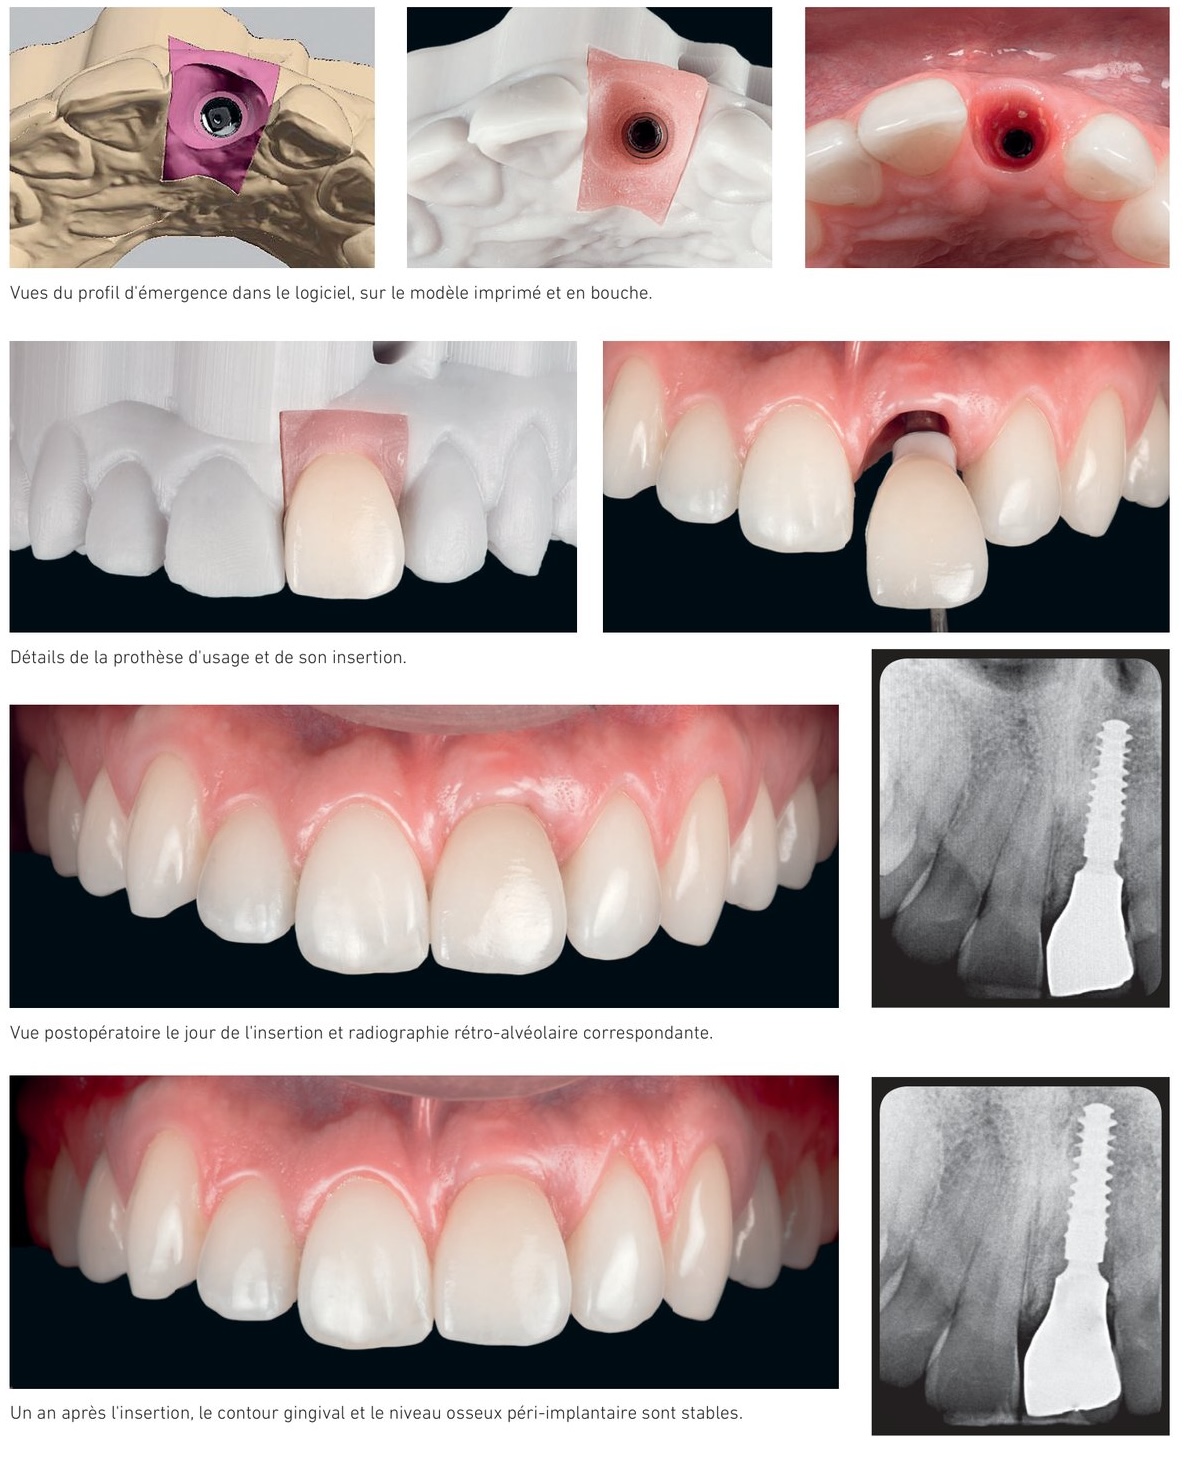

Situation clinique 1 — profil d'émergence, prothèse d'usage et résultat à 1 an

Situation clinique 1 — vue du profil d'émergence en bouche, insertion et radiographie de contrôle

Patient de 32 ans, fracture radiculaire verticale de l'incisive centrale maxillaire gauche. Protocole d'implantation et temporisation immédiate avec guide chirurgical, implant BLX® 3,75 × 12 mm (45 N.cm), greffon de tissu conjonctif et comblement à la Bio-Oss®. La couronne provisoire est numérisée selon le protocole E-Merge dès le jour de la chirurgie. À trois mois, la restauration définitive est insérée sans aucune déconnexion de la provisoire.